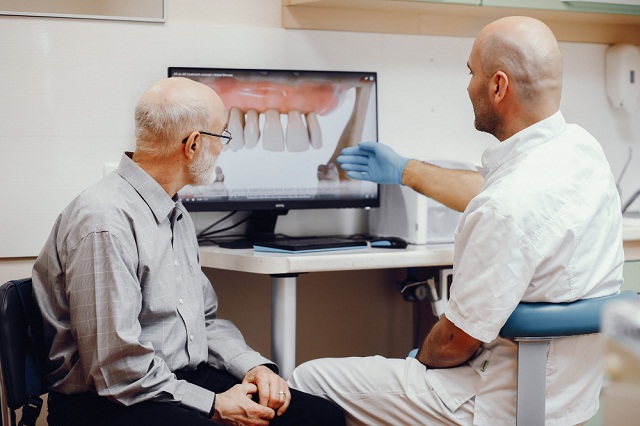

Why do Patients trust us

Expert Dentistry for a Healthy and Bright Smile

We are committed to providing personalized & high-quality dentistry using modern techniques, so you can have a lifetime of healthy and confident smiles.

- Modern solutions for healthy teeth

- Complete dental care for all ages

- Focused on long-term oral health

- Safe and accurate full-mouth X-rays

- Gentle and effective dental cleaning

- Experienced and certified dentists